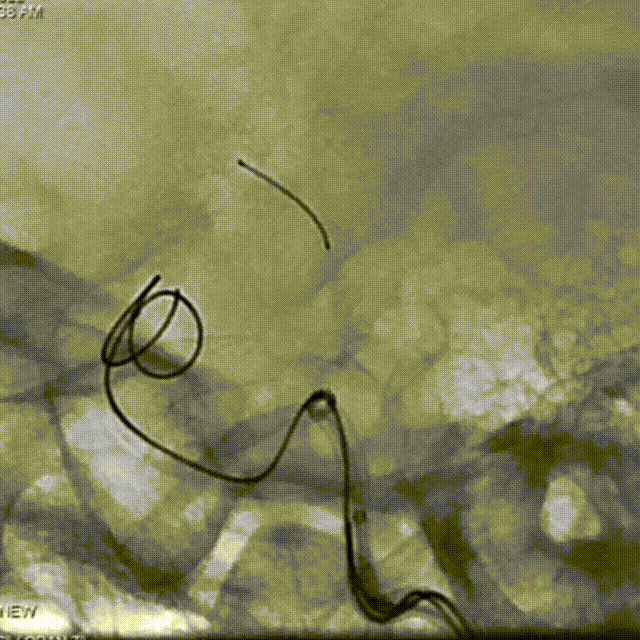

治疗过程

支架导管及弹簧圈微导管先后超选到位,其中弹簧圈微导管超选入远端眼动脉段动脉瘤内备用,根据测量结果,选用YonFlow®血流导向密网支架 4.5mm/30mm、弹簧圈9mm/40cm,先部分推出弹簧圈在动脉瘤内提供保护。再释放密网支架。